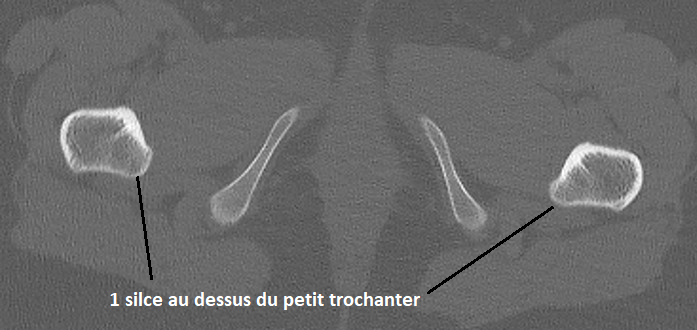

Coupes

A

Tête fémorale